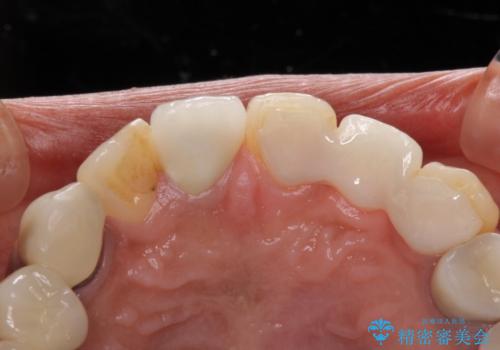

前歯の裏側の接着面は、隙間ができていたことにより、汚れがたまるだけでなく、むし歯にもなっていました。

我々としては、治療により状態が悪化することだけは避けたいと考えているため、歯全体を覆うクラウンにすることで、より長持ちする治療を提供いたしました。

外観はもちろんのこと、隙間なく安心して咬むことのできる前歯となり、患者様には大変満足していただきました。